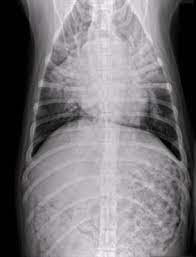

X rays are very helpful in the diagnosis of lung cancer in dogs. If you have lung cancer, it may be more difficult for your doctor to diagnose pneumonia. A white spot amidst the normal black lungs can therefore be a cancer, infection. Dog pneumonia or lung cancer. Pneumonia is a lung infection that leads to breathing difficulties and fluid in the lungs.

A definitive diagnosis of lung cancer requires a sample of tissue (biopsy). X rays are very helpful in the diagnosis of lung cancer in dogs. Primary lung cancer are frequently located in the caudal (towards the hind end of the pet) lung lobes, however can be located in any lung lobe and are usually a single mass in the lungs, unless the tumor has spread. If your dog has a chronic cough, you'll need to rule these out. The first of these possibilities could be investigated by bronchoscopy. A definitive diagnosis of lung cancer requires a sample of tissue (biopsy). The second kind of lung cancer in dogs is called metastatic lung cancer, which means the cancer originated somewhere else in the body, but has spread to the lung. Bacterial pneumonia is an inflammation of the lung usually caused by bacterial or viral infection but can be caused by inhalation of an irritant. The respiratory system consists of the large and small airways and the lungs. Lung cancer is actually the number one killer when it comes to cancers. But in some rare cases, it may be a lung cancer (primary or secondary). In both cases, you may have. Typical signs of bacterial pneumonia include fever, difficulty breathing, lethargy and coughing.

Primary lung cancer are frequently located in the caudal (towards the hind end of the pet) lung lobes, however can be located in any lung lobe and are usually a single mass in the lungs, unless the tumor has spread. My dog had pneumonia come on quickly this last august, we took her to the local er at 3am when we noticed her breathing labored and strange behavior. A white spot amidst the normal black lungs can therefore be a cancer, infection. Signs of the primary tumors in dogs. I haven't touched cigarettes a day in my life. Lung cancer often misdiagnosed as pneumonia urges requests for second medical opinions. Lung cancer is actually the number one killer when it comes to cancers. A definitive diagnosis of lung cancer requires a sample of tissue (biopsy). His appetite is basically normal though his blood work shows that he is anemic. 3 doctors agree send thanks to the doctor Other common respiratory diseases that might make you worried about cancer are …. Malignant tumors trigger inflammation in surrounding normal lung tissue, and they may obstruct. Pneumonia and lung cancer both affect the lungs but one is easily treatable and the other is potentially life threatening.